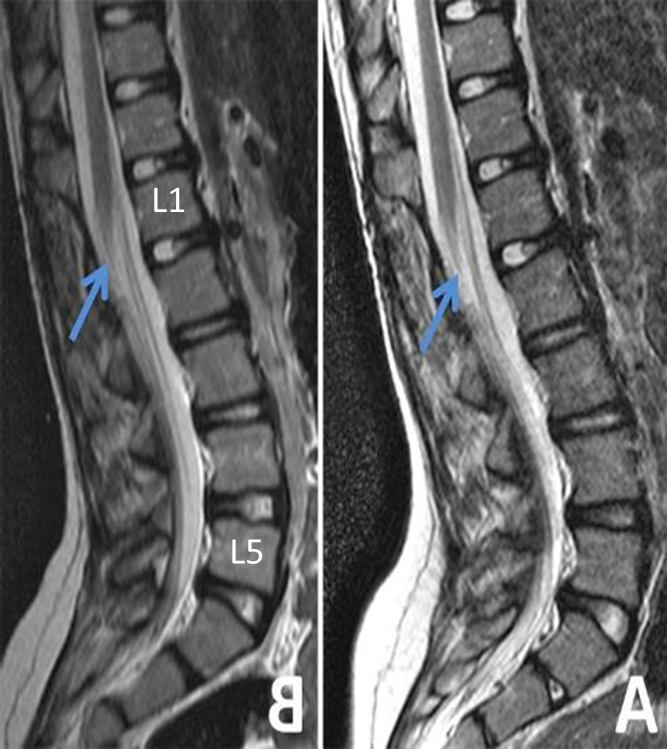

Spinal cord ends around ___

L1

The tip of the conus medullaris descends to the inferior limit of the __ vertebral body

Spinal cord images